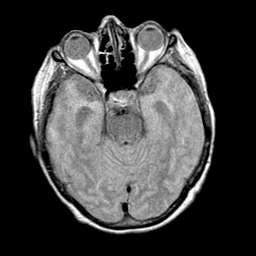

Pick's Disease, MR Study mr-pd -- Slice #7

[Home][Help][Clinical] Slice 7